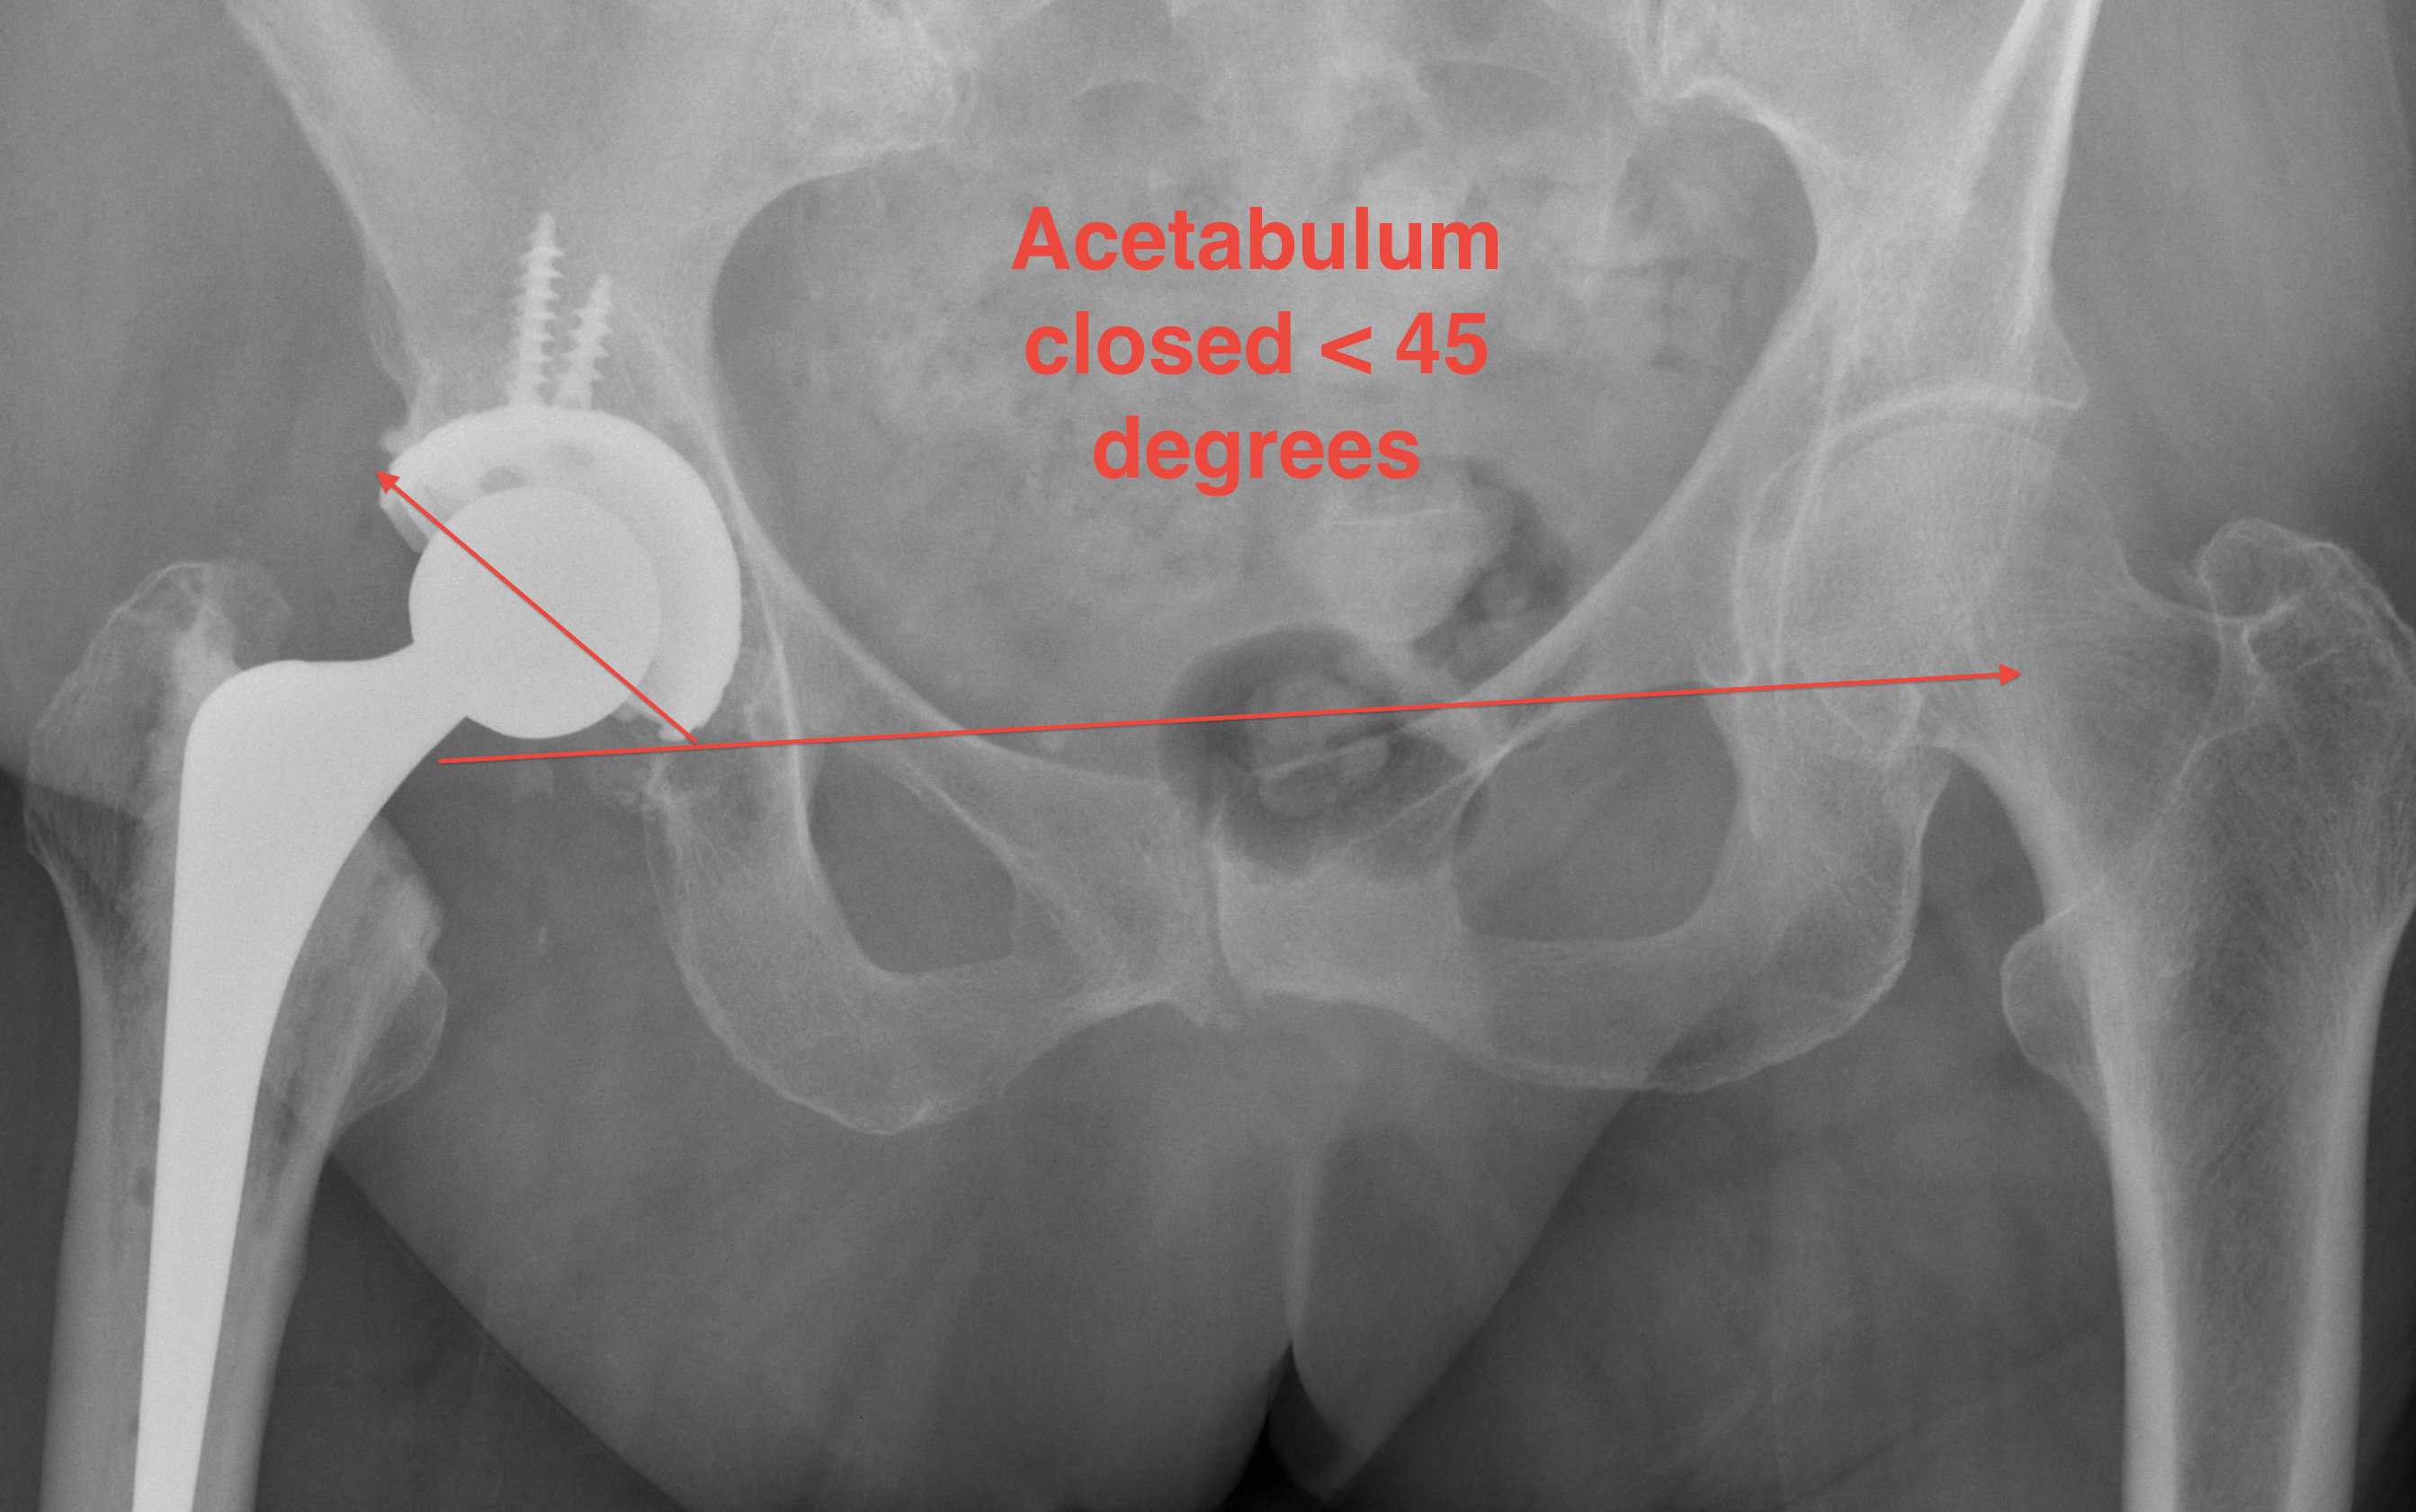

1. Acetabular Inclination

AP Xray

Excessive acetabular inclination